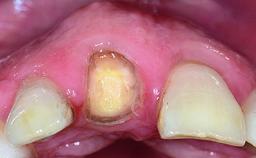

Replacement of an Ankylosed Upper Left Central Incisor: Bone Augmentation and Socket Grafting, Late Placement of an RC Bone Level Implant

Abutment Type CAD/CAM

Prosthesis Type FDP

Provisional Implant-Supported Prosthesis Prosthodontic margin > 3 mm apical to mucosal margin Prosthodontic margin > 3 mm apical to mucosal margin